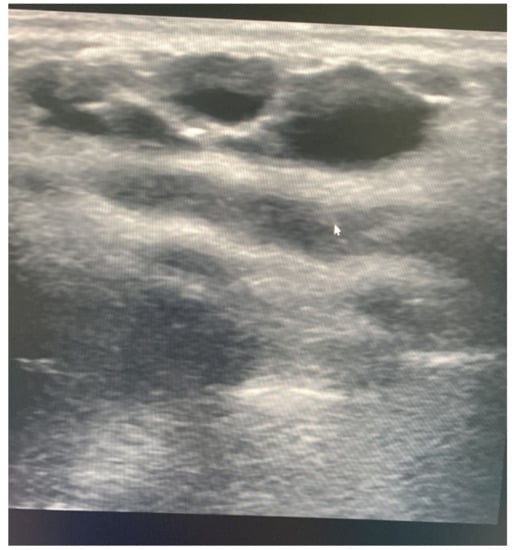

Sudden Appearance of a Palpable Chest Wall Mass Secondary to Macrocystic Lymphatic Malformation: A Case Report

2. Case Report